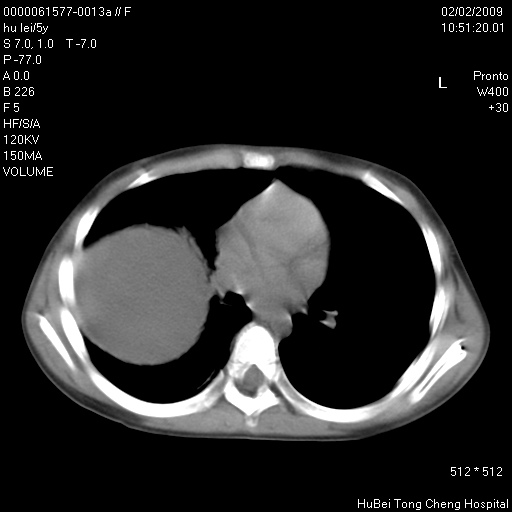

标题: PED1732:M5Y,右肺囊性占位!

患者:男,5。无明显不适,拍胸片考虑右肺囊肿。

行ct扫描,图象如下:

病灶与前胸壁和右上纵隔、叶间裂界限不清,病灶前缘及内侧缘看不到正常的肺组织,不能排除包裹性积液。